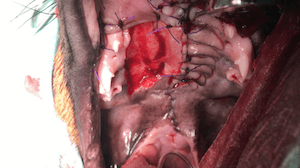

Soft Tissue Sarcoma

2 attempted removals by referring vet. Regrowth within 2 weeks.